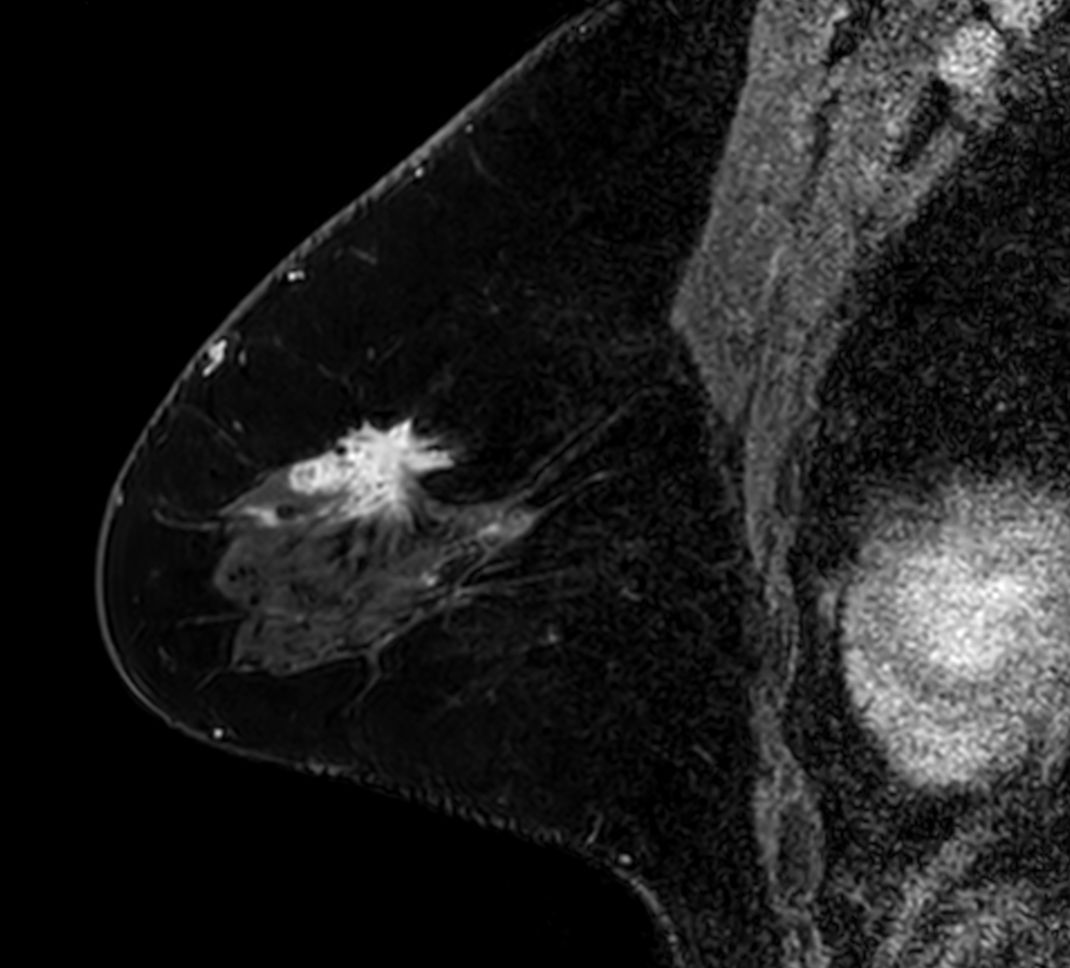

3D mDIXON XD +gado (right breast) Compressed SENSE

-